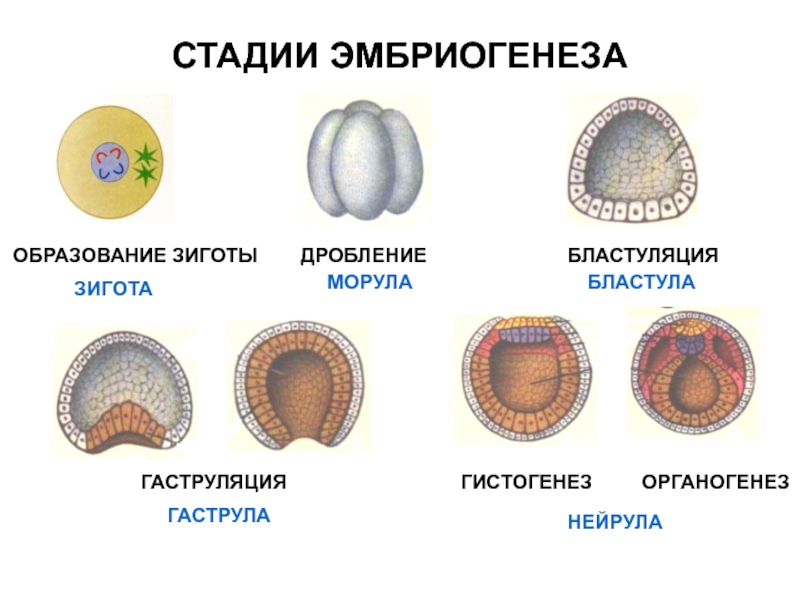

Эмбриональный период: Развитие эмбриона от зачатия до рождения